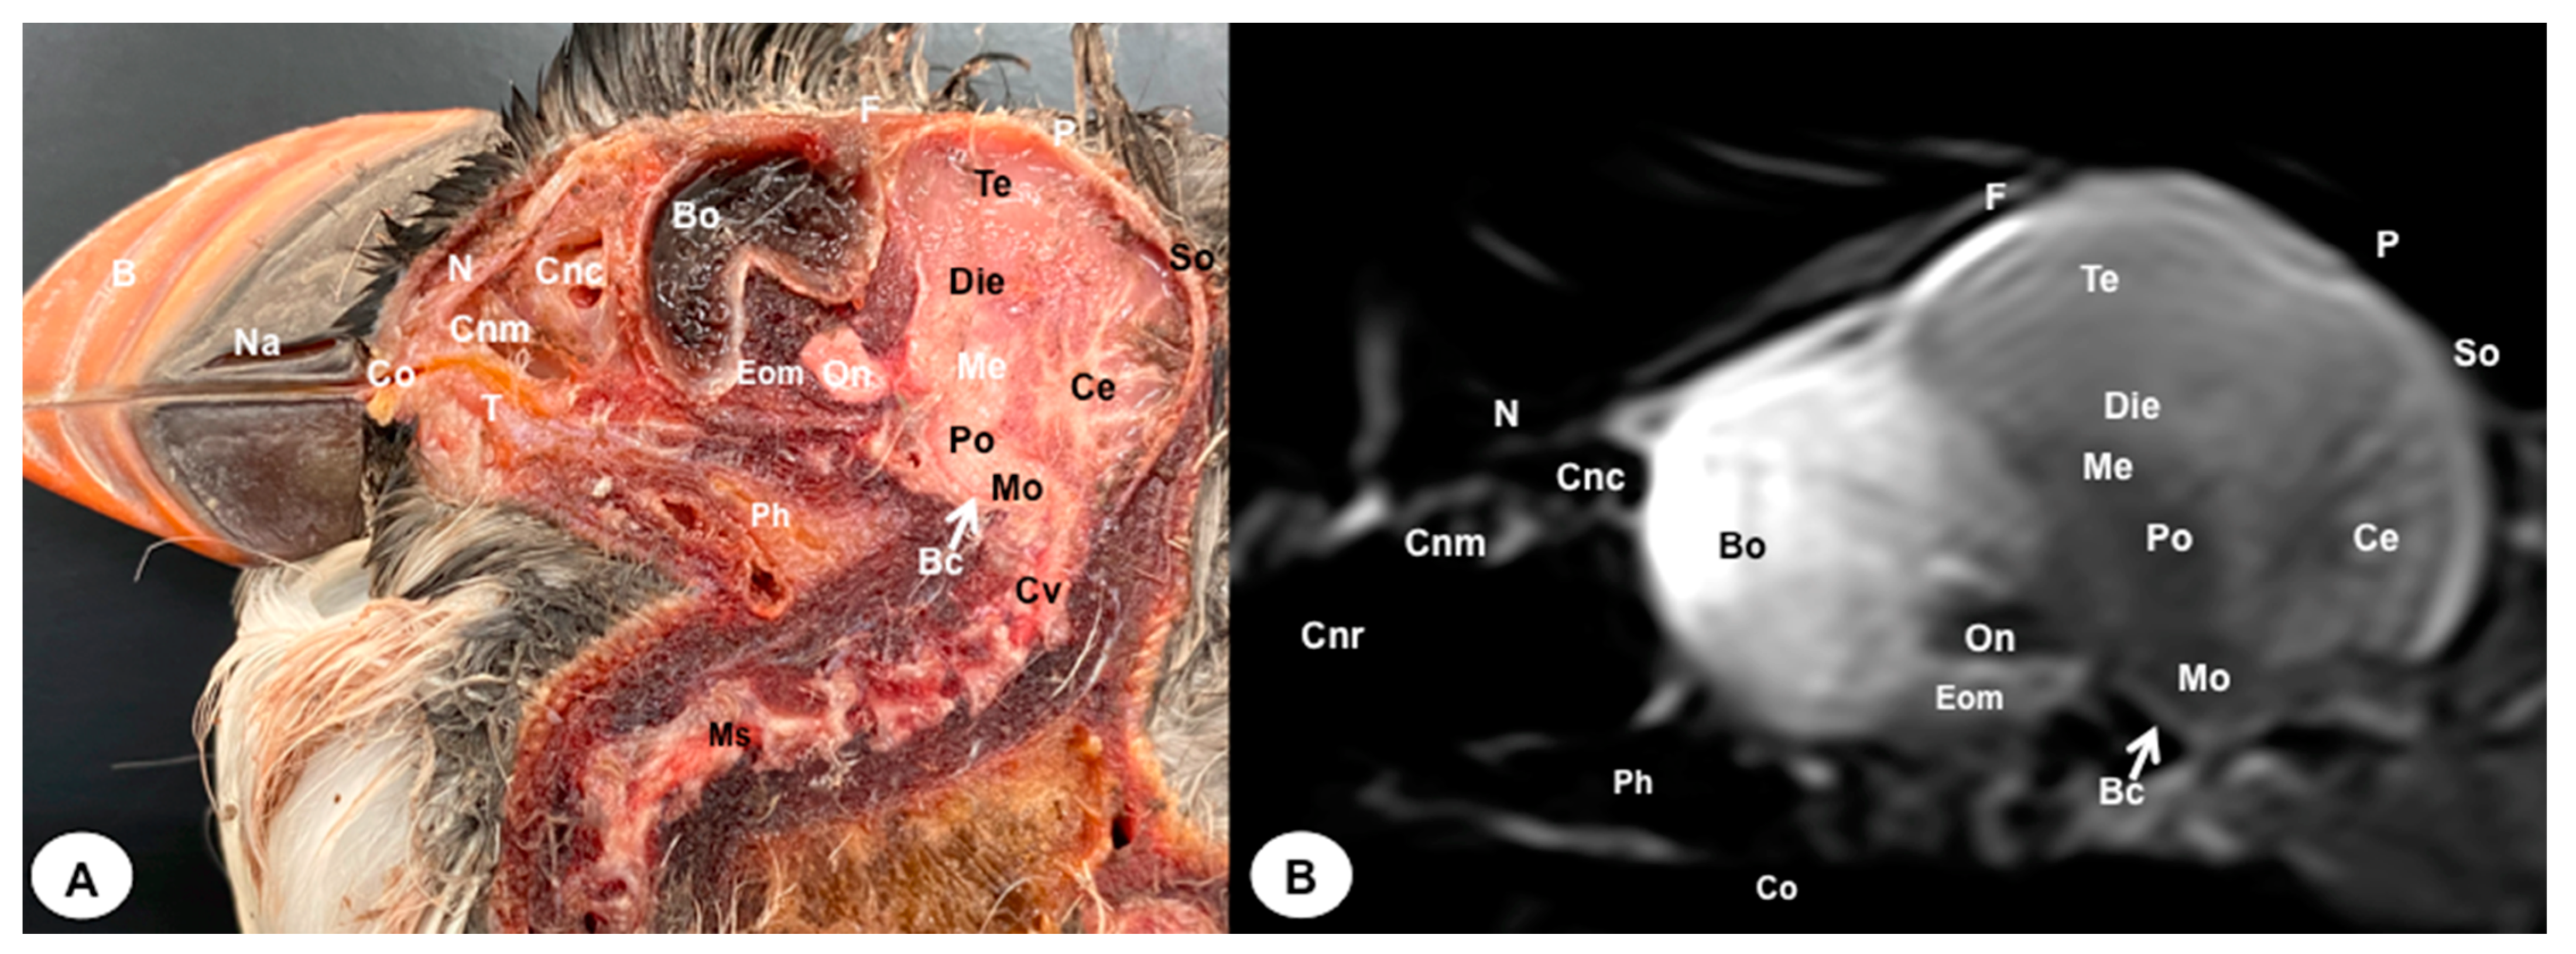

3.1. Anatomical Sections

3.2. Magnetic Resonance Imaging (MRI)